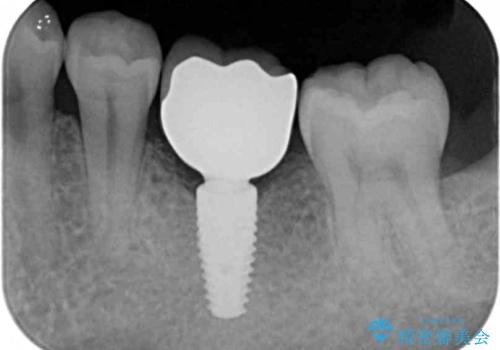

- 46.2万円(仮歯・ストローマンインプラント・チタンカスタムアバットメント・ジルコニアクラウン)費用は治療当時の料金となります

減ってしまった顎骨に増骨処置を行うことで、より安定した環境で長く使用できるようなインプラント治療を行っています。